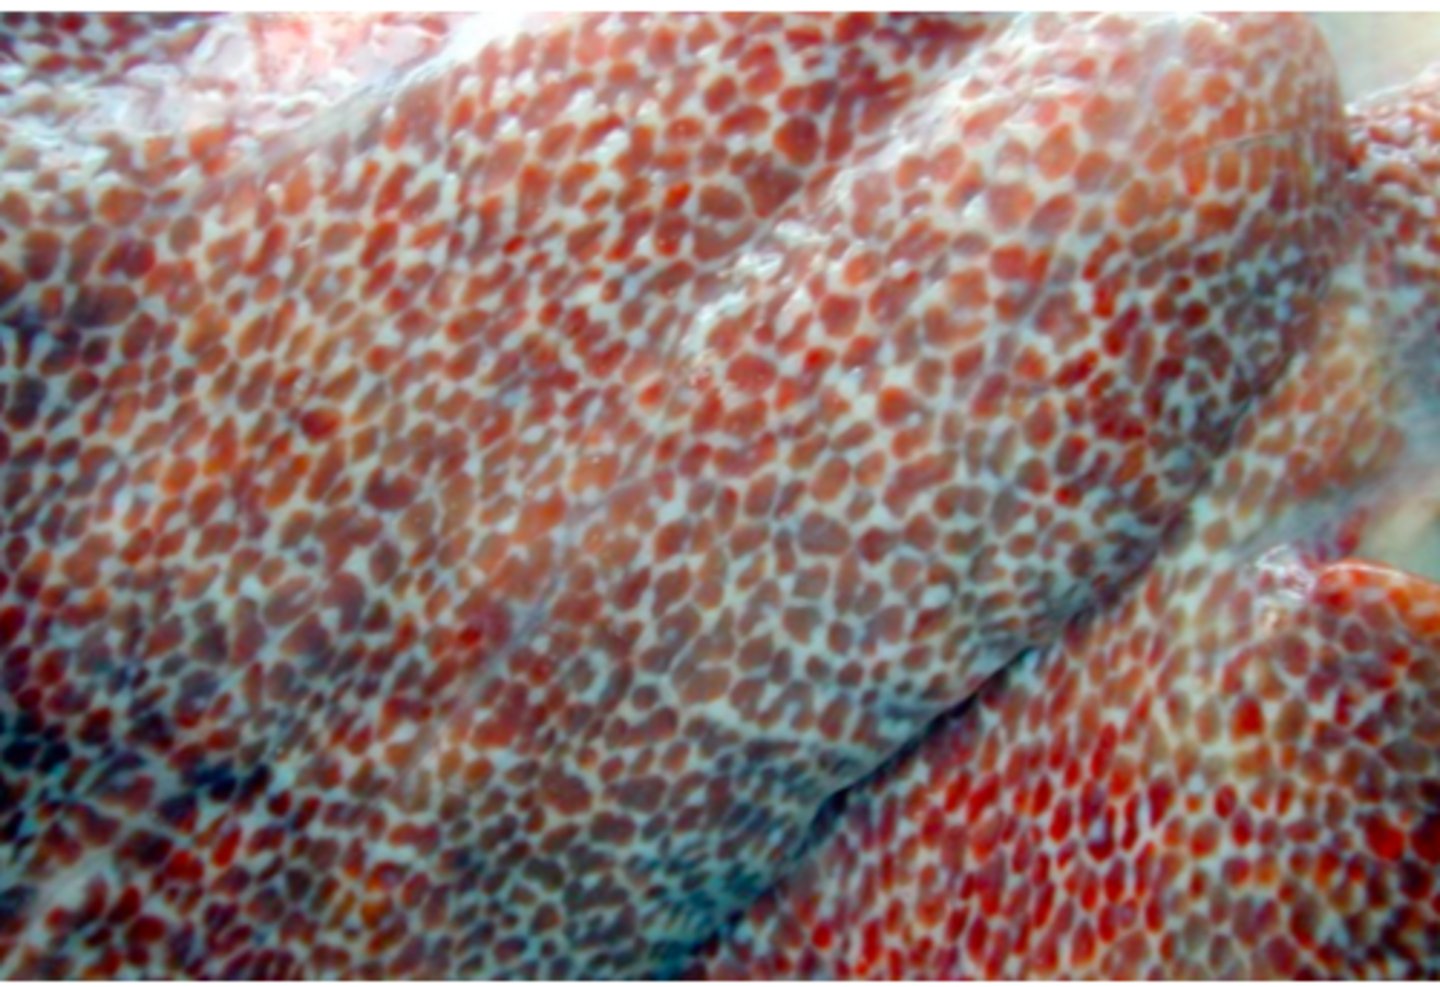

Lever fra okse, hvad er den patoanatomiske diagnose?

kronisk fibroniserende cholangioheptatitis (pile)

Ætiologi: Dicrocoelium dendriticum (den lille leverikte)

Lever fra får, hvad er den patoanatomiske diagnose og ætiologien?